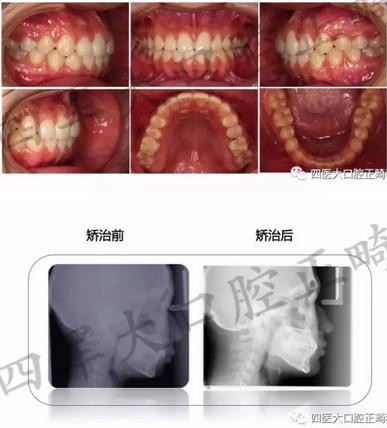

在剛剛閉幕的“絲綢之路口腔正畸學(xué)術(shù)年會暨疑難錯合畸形多學(xué)科綜合診治研討會”上,我們隆重舉辦了一年一度的四醫(yī)大口腔正畸科青年醫(yī)師病例展示,各路新俊都大顯身手。小編會分五輯為您呈現(xiàn)每位青年醫(yī)生的精彩病例片段,歡迎各位患者及同行朋友圍觀

來源:四醫(yī)大口腔正畸科